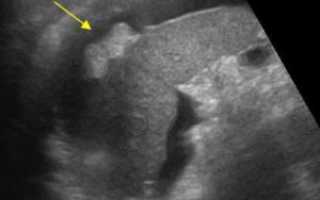

Исследование брюшной полости и забрюшинного пространства (ЗБП) позволяет провести тщательный осмотр не только органов ЖКТ (желудочно-кишечного тракта) и мочевыделительной системы, но и находящихся здесь кровеносных сосудов. В ходе процедуры отчетливо визуализируются паренхиматозные (плотные) ОБП, при использовании допплерографии удается изучить кровообращение в крупных сосудах и более мелких, питающих сами органы.

Пациент лежит на кушетке, на спине. Врач-узист наносит специальный гипоаллергенный гель на кожу живота пациента (для улучшения контакта) и датчик прибора, затем начинает осмотр. В некоторых областях живота датчик под нажимом руки врача как бы углубляется внутрь, обеспечивая максимально близкое расстояние с органом.

Иногда, для улучшения видимости исследуемого участка, например, печени и селезенки, скрытых под реберной дугой, необходимо будет сделать глубокий вдох и задержать дыхание. В этот момент органы немного смещаются книзу, что способствует их лучшей визуализации.

Ультразвуковые волны легко проходят через кожные покровы, отталкиваются от изучаемого органа и отображают результат на мониторе черно-белой картинкой. Для лучшего контакта с датчиком на кожу пациента наносится специальное гелеобразное вещество.